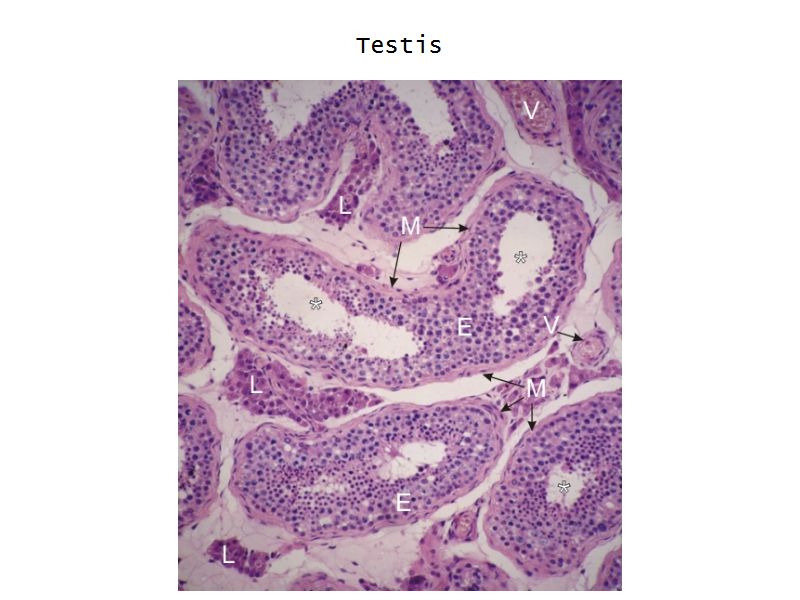

Testis

Slide 84

Testis

- Tunica albuginea

- Lobuli

- Seminiferous tubuli

- Epididymus

- Ductus deferens

Tunica albuginea

- Thick fibrous CT capsule

- Forms septae

- Divide testis into lobuli

Lobuli

- Pyramidal shaped compartments

- Contain 1 - 4 seminiferous tubules each within

- Meshwork of loose CT

- AVN

- Leydig cells

Leydig cells

- Interstitial cells

- Surrounded by rich AVL

- Large round - polygonal shape with clear cytoplasm

- Large central nucleus

- Endocrine - testosterone

Seminiferous tubuli

- Site of spermatozoa production

- 150 - 250 µm diameter

- Complex stratified epithelium

- Blood-testis barrier

Seminiferous epithelium

- Two types of cells

- Spermatogenic cells

- Sertoli cells

- 4 - 8 cell layers thick

- Forms the blood-testis barrier

Sertoli cells

- Complex columnar shape

- Basal lamina to lumen

- Irregular outline

- Envelope developing germ cells

- Large pale nucleus with indentations & large nucleolus

- Occludens junctions with adjacent cells

- Establish blood-testis barrier